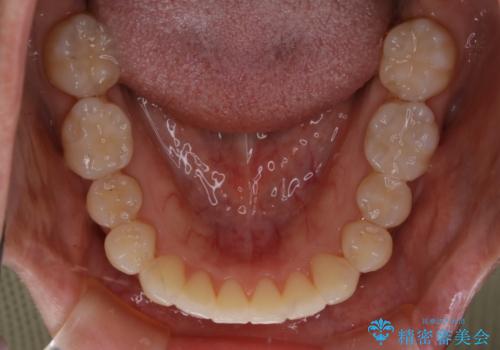

- 右上の2番目の歯が内側に入っているのと、下の前歯のがたつきが気になるとご相談にいらした方です。

上下左右の歯を後ろに動かして歯を並べるスペースを確保し、内側に入っていた歯を綺麗に並べ、前歯の中心もお顔の中心に合うようにしました。

矯正用アンカースクリューを埋入し、上下左右の歯を後ろに動かすことで歯を並べるスペースを作りました。

元々内側に倒れていた右下の奥歯は、ゴムかけを追加で行っていただくことによりしっかり起こすことが出来ました。

歯並びが綺麗になったことでモチベーションが上がり、銀歯からセラミックへのやり替えも行っております。